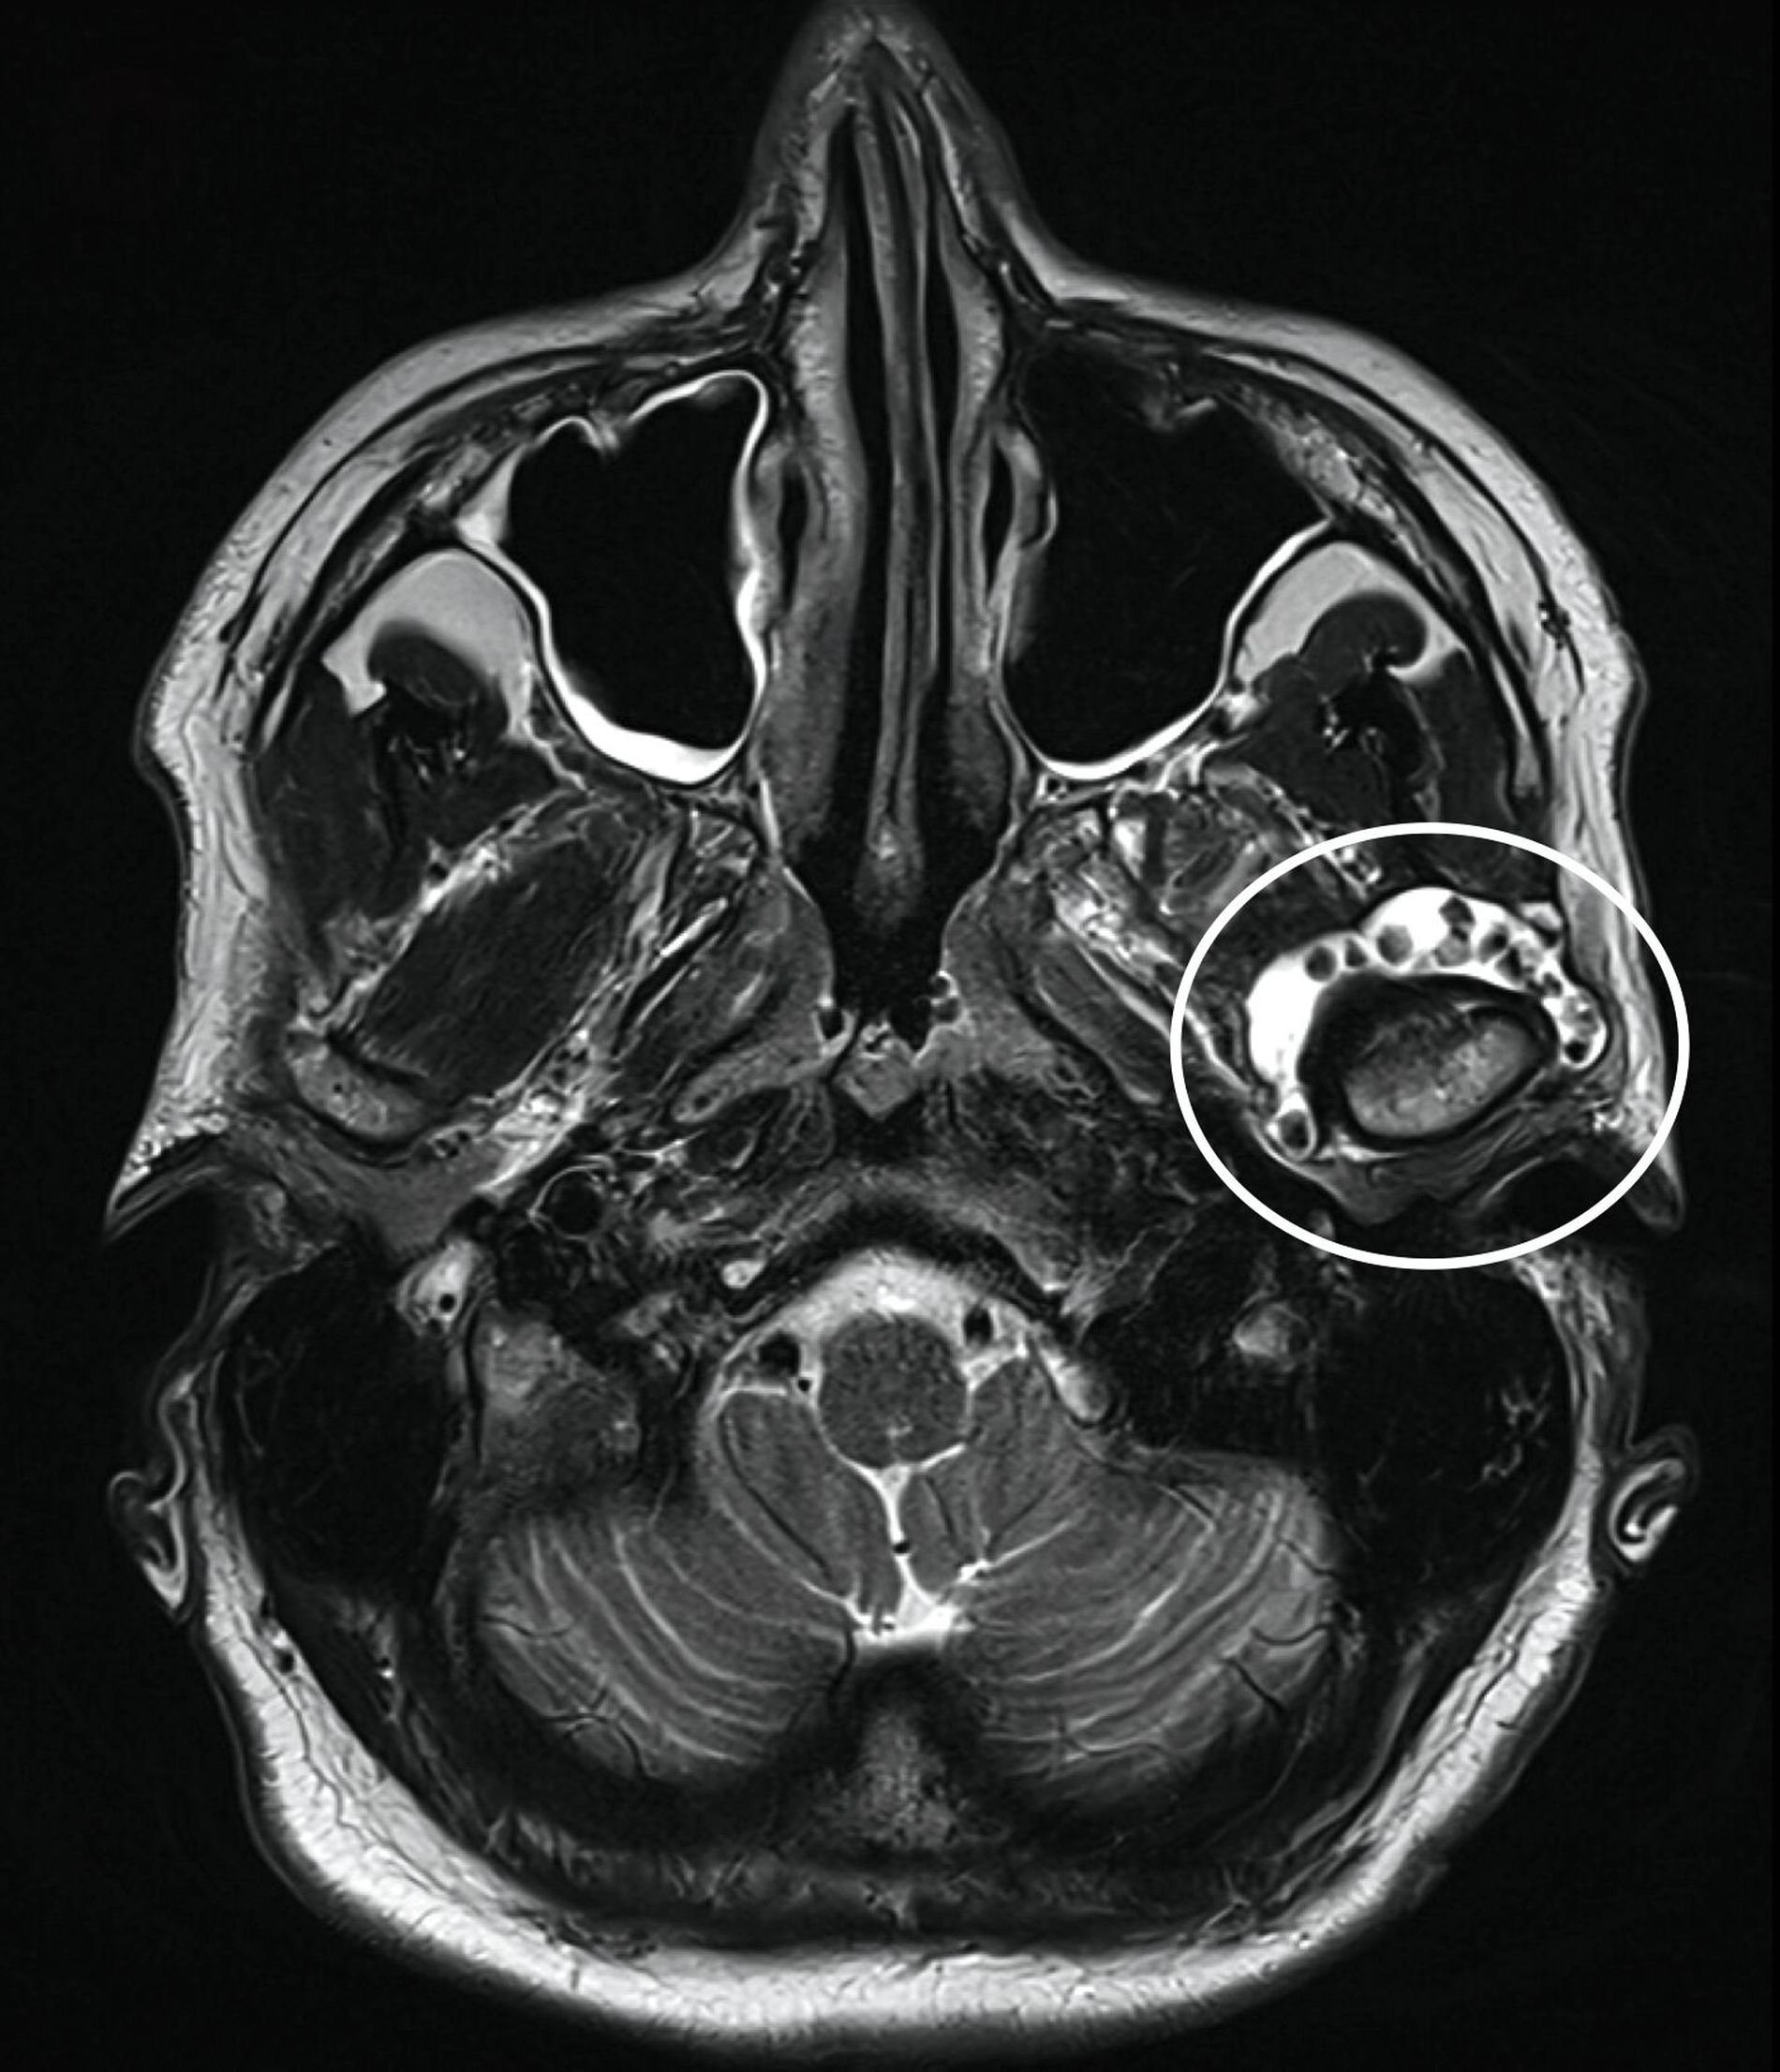

Klinisch zeigte sich kein Hinweis auf eine Myopathie der Kaumuskulatur. Zudem waren weder eine Mundöffnungsbehinderung noch ein Kiefergelenkgeräusch detektierbar. In Anbetracht der klinischen und der radiologischen Verdachtsdiagnose wurde eine Magnetresonanztomografie durchgeführt (Abbildung 2), die eine deutliche Flüssigkeitskollektion zirkulär im Bereich des linken Kiefergelenks mit multiplen, a. e. hyalinen Fragmenten sichtbar macht.

Bei nunmehr erhärteter radiologischer Verdachtsdiagnose auf das Vorliegen einer synovialen Chondromatose erfolgte, entsprechend dem Patientenwunsch, die offen-chirurgische Resektion der multiplen Gelenkkörper in Intubationsnarkose. Der Zugang wurde klassisch präaurikulär mit einer temporalen Extension zum Schutz des Ramus temporalis des Nervi facialis gewählt (Abbildung 3a). Unmittelbar nach Eröffnung der Kiefergelenkkapsel entleerten sich rasch mehrere kleine, knorpelige Raumforderungen (Abbildung 3b), die im Rahmen des Eingriffs vollständig entfernt wurden (Abbildung 3c). Der erweiterte, nun leere obere Gelenkspalt ist in Abbildung 3d dargestellt.